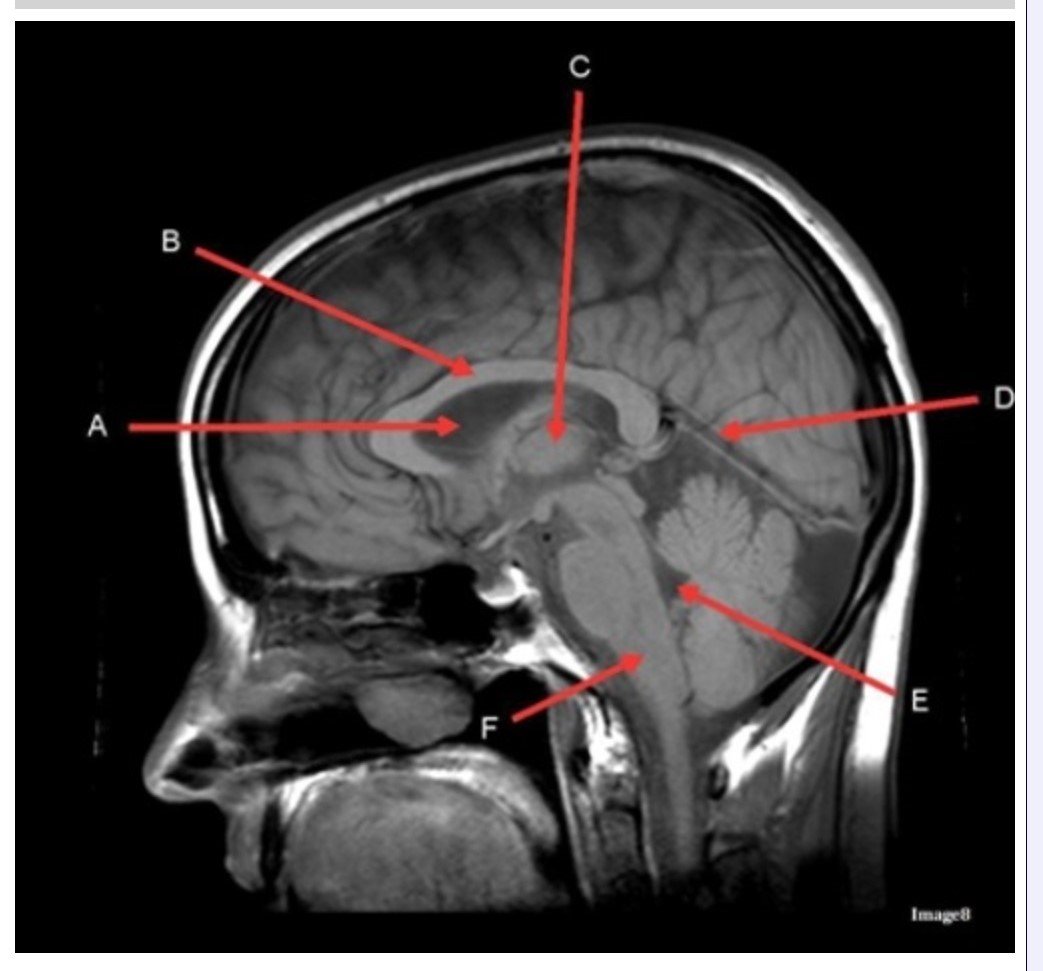

Letter C in Image 8 is pointing to:

A. Tentorium

B. Corpus callosum

C. Thalamus

D. Fourth ventricle

E. Medulla oblongata

Letter F in Image 8 is pointing to:

A. Tentorium

B. Cerebellum

C. Thalamus

D. Fourth ventricle

E. Medulla oblongata

Letter A in Image 8 is pointing to:

A. Tentorium

B. Corpus callosum

C. Hypothalamus

D. Fourth ventricle

E. Lateral Ventricle

Letter E in Image 8 is pointing to:

A. Tentorium

B. Cerebellum

C. Thalamus

D. Fourth ventricle

E. Medulla oblongata

Letter B in Image 8 is pointing to:

A. Tentorium

B. Corpus callosum

C. Hypothalamus

D. Fourth ventricle

E. Medulla oblongata

Letter D in Image 8 is pointing to:

A. Tentorium

B. Cerebellum

C. Thalamus

D. Fourth ventricle

E. Medulla oblongata

Image 8 is an example of a _______ weighted sequence acquired in the _______ scan plane.

A. T1; Axial

B. T1; Sagittal

C. T2; Axial

D. T2; Sagittal